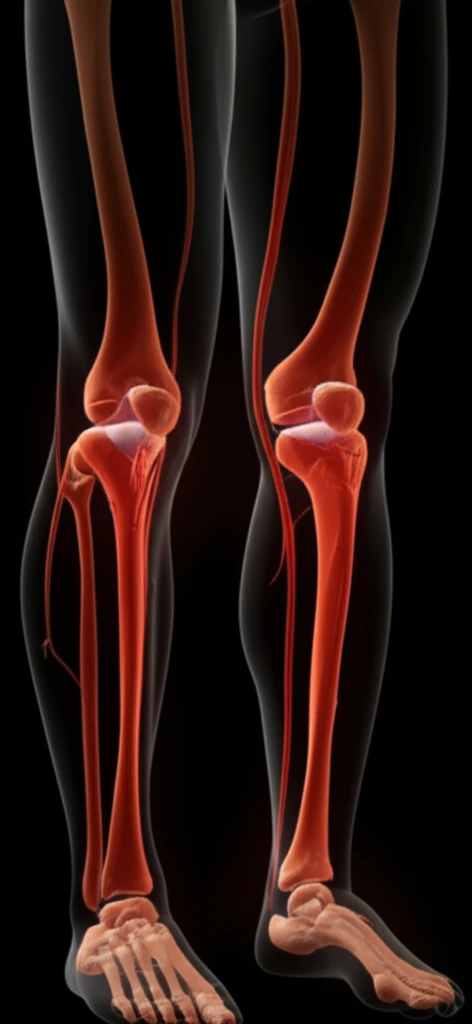

Peripheral artery disease (PAD) affects millions, often leading to pain and reduced mobility. Traditional diagnosis relies on methods like contrast-enhanced magnetic resonance angiography (MRA), which uses gadolinium-based contrast agents. However, these agents pose risks, especially for individuals with kidney problems.

This article explores the accuracy of non-contrast MRA protocols at 3T (Tesla) for detecting and characterizing lower extremity PAD. We'll delve into how these techniques compare to gadolinium-enhanced MRA, providing insights into their effectiveness and potential benefits for patients.

Non-contrast MRA utilizes various techniques to visualize blood vessels without contrast agents. These methods rely on the natural properties of blood flow and magnetic fields to create images of the arteries. Two established non-contrast MRA protocols are quiescent-interval single-shot (QISS) and a combination of quadruple inversion recovery (QIR) with electrocardiogram-gated fast spin echo (ECG-FSE).